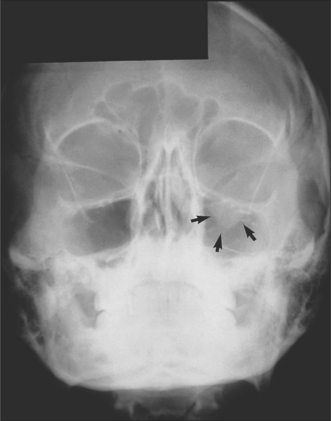

mid-face: two occipitomental views at different angles (Fig. 13.6)

tooth-bearing areas of the jaws: orthopantomogram and posteroanterior (Figs 13.7, 13.8)

Fig. 13.6 Occipitomental view of fractured zygoma. Arrows indicate fractures at the infraorbital rim, zygomatic arch and zygomatic buttress areas.

Radiographs may be necessary not only to reach a diagnosis but also to inform treatment decisions, for example, about where bone plates should be applied. They also commonly reveal injuries which may not need treatment, for example, undisplaced or minimally displaced fractures, medial blow-out fractures of the orbit and comminution of the mid-face. Radiographs provide much more detailed information on hard-tissue injuries than the clinical examination so they may, for example, show fractures of the roots of teeth and signs of associated soft-tissue abnormality, such as herniation of orbital contents into the maxillary antrum (Figs 13.9, 13.10).

Fig. 13.9 Occipitomental view of a fracture of the left orbital floor. Note the herniated orbital contents, outlined by the arrows.